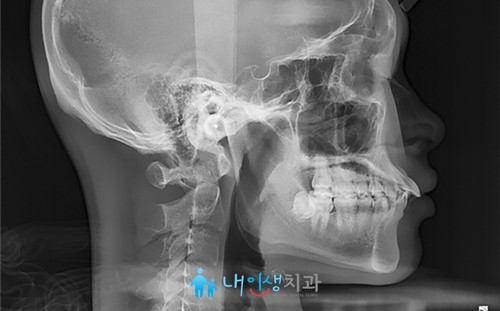

처음 저희 병원을 방문해 주신 날

촬영한 X-ray 사진입니다. 위 앞니가 심하게 뻐드러져 있고

이로 인해 돌출입 증세를 보이셨어요.